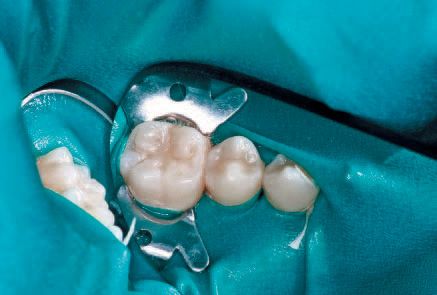

No local anesthesia is necessary, but rubber dam isolation is recommended to assist in the success of the ICON resin infiltration procedure. Cleanse the isolated tooth with NaOCl or Consepsis and rinse thoroughly with a water spray and air dry. The teeth are separated using one of the enclosed plastic wedges, which will allow for the placement of the Proximal-Tip foil matrix delivery system. The wedge can be maintained interproximally during the entire procedure if necessary (Fig. 5).

Screw one of the Proximal-Tips onto the end of the ICON-Etch (15% HCl), insert it between the teeth with the green side facing the affected proximal lesion, and turn the shaft 1½ to 2 turns to deliver the etchant. Leave the ICON-Etch on the surface for 2 minutes (Fig. 6).